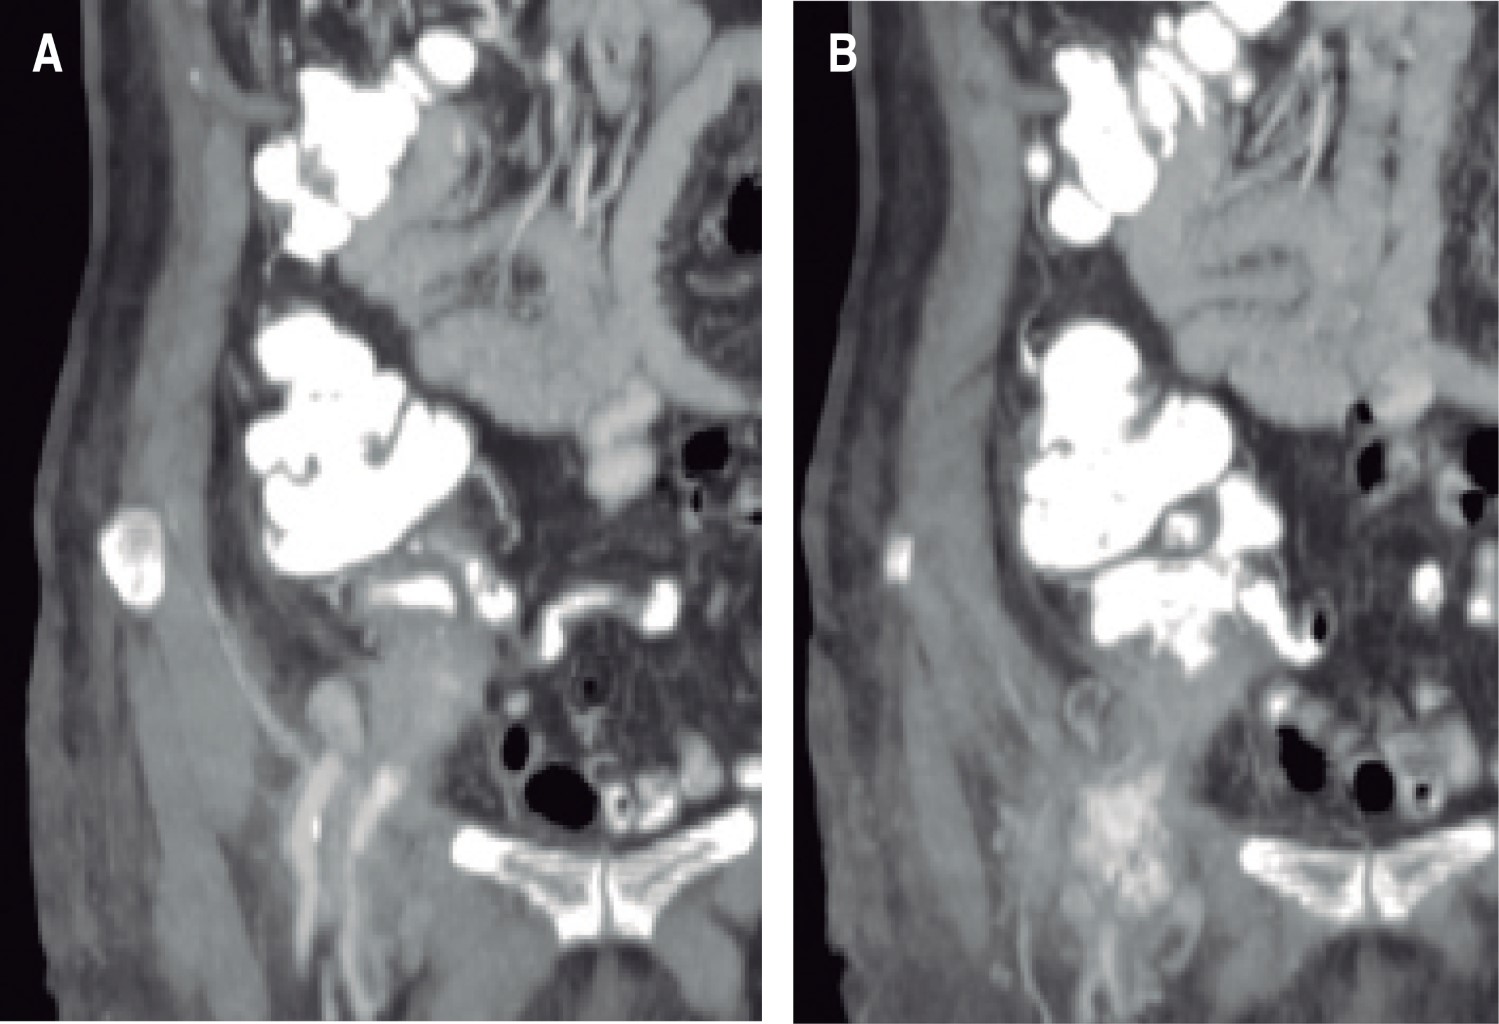

An 84-year-old woman with a history of systemic arterial hypertension and chronic atrial fibrillation controlled with enalapril and verapamil. Within her surgical history, four years prior to the current condition, she underwent emergency surgery for a right direct strangulated inguinal hernia, with intestinal content, approached in the inguinal region, requiring intestinal resection and entero-entero-terminal anastomosis and Shouldice hernioplasty. Her postoperative period was satisfactory, and she was discharged without complications. Her current condition began with a mass in the inguinal region, which was growing slowly, initially presenting with dull mild pain. She did not give it importance. In the following two weeks she noticed an important growth in the zone with changes in color, erythema, and intense pain, so she went to another hospital where a strangulated inguinal hernia was suspected again. An ultrasound scan was performed in the inguinal region, which reported an apparent inguinal hernia and abundant gas, which was avascular according to the Doppler function. She was sent to our institution for management. On examination she was agitated, tachycardic (105 beats per minute) and moderately dehydrated. On abdominal examination a rigid, erythematous, and warm mass was found in the right inguinal region, which displaced the previous surgical scar. It was very painful on palpation. She had leukocytosis of 19,250 cells/µl with neutrophilia of 88.90%, increased prothrombin time (PT) and partial thromboplastin time (PTT), and the rest of her lab tests were within normal rages. A recurrent inguinal hernia with intestinal content was suspected, although the appearance of the mass was reminiscent of an abscess (Figure 1). It was decided to take her to the operating room where, under regional anesthesia, an incision was performed through the previous scar. A large abscess approximately of 400 cm3 was found and was completely drained. The previous inguinal plasty was observed intact. No hernial sacs were observed. The origin of the abscess could not be clearly determined. It was decided to use the open wound technique with closure by second intention and keep on monitoring the patient. Cures were performed according to the output and a contrasted abdominal tomography scan was performed a few hours later to determine the probable sites of origin of the abscess. At this moment, a complicated diverticular disease was suspected. The report by the imaging service staff was of an edematous vermiform appendix, which apparently comes out through the femoral duct and a small peri-appendicular collection (Figure 2). A new exploratory laparotomy was scheduled where multiple adhesions around the site of the anastomosis performed four years ago were found. These adhesions were released reaching the cecum and vermiform appendix (Figure 3). An appendicectomy was performed with management of the Pouchet stump. When the surgical specimen was removed the appendix tip was found completely perforated. The closure of the hernial defect was attained with two simple polypropylene 00 stitches. It was decided not to place a prosthetic mesh due to the high risk of infection. The postoperative period was satisfactory, with a decrease in leukocytosis to 9.43 cells/µL and normalization of PT and PTT. The total hospital stay was six days. The inguinal wound granulated by second intention, continuing with cures and weekly supervision until total closure was achieved. The final histopathological was of an acute appendicitis with leukocyte infiltration in greater quantity in its distal half, lymphoid hypertrophy in its proximal half, a perforated tip and negative for malignancy (Figure 4).

Figure 2